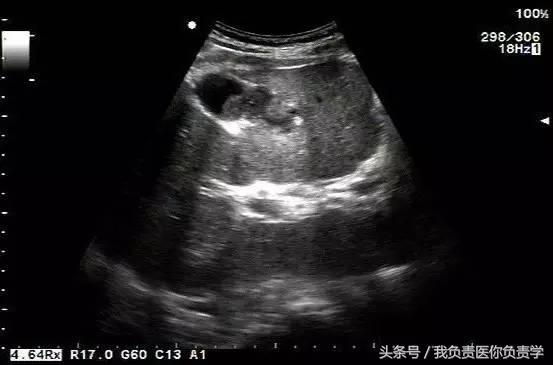

典型病例 1

患者男,64岁,因右上腹疼痛半月余就诊。查体发现右上腹部轻压痛,无发热。超声检查所见如下:

图1示胆囊增大,囊壁增厚,囊内透声差

图2示于胆囊外侧可见一局限性囊性无回声区

图3示胆囊与囊性回声区间隐约可见裂隙相通

图4和5为局部放大图像,可见胆囊与囊性回声区间可见直径约2mm的通道

超声检查考虑为胆囊炎合并胆囊穿孔,后经CT检查证实。